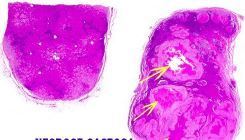

FIBROSE, na pancreatite crônica

Observar a Fibrose e a calcificação

Calcificação e fibrose na pancreatite crônica, como forma de reparo/cicatrização ao parênquima lesado pela inflamação